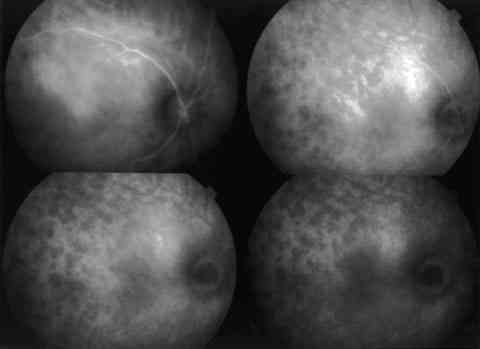

Figura 4

ICGA OD: MANCHAS HIPOFLUORESCENTES DISPERSAS. HALO HIPERFLUORESCENTE PERIPAPILAR.